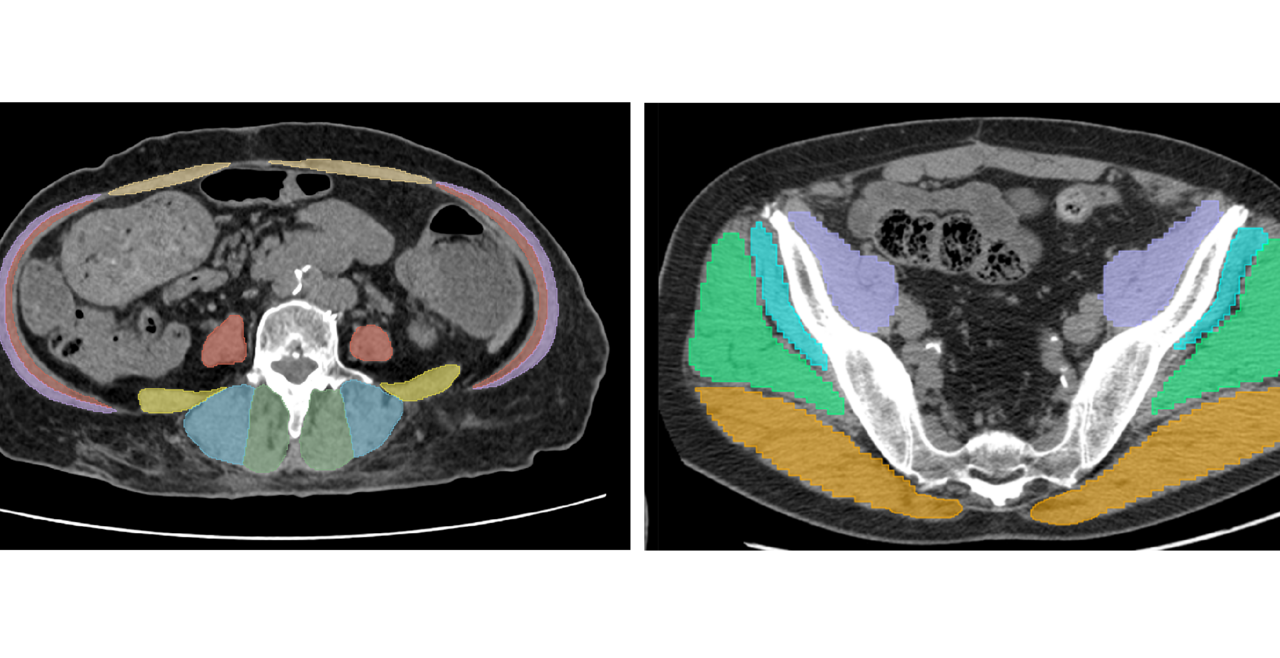

Muscle Assessment